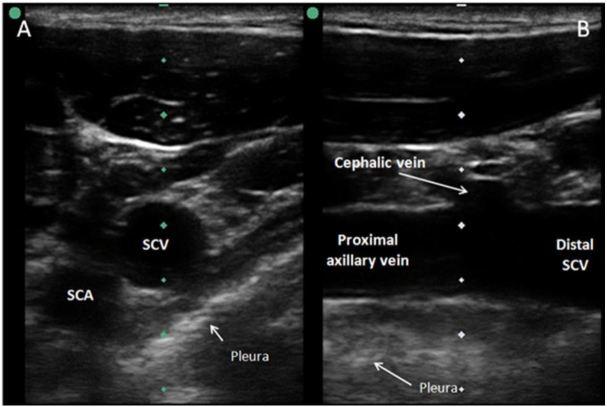

Despite multiple advantages, subclavian vein (SCV) cannulation via the traditional landmark approach has become less used in comparison to ultrasound (US) guided internal jugular catheterization due to a higher rate of mechanical complications. A growing body of evidence indicates that SCV catheterization with real-time US guidance can be accomplished safely and efficiently. While several cannulation approaches with real-time US guidance have been described, available literature suggests that the infraclavicular, longitudinal "in-plane" technique may be preferred. This approach allows for direct visualization of needle advancement, which reduces risk of complications and improves successful placement. Infraclavicular SCV cannulation requires simultaneous use of US during needle advancement, but for an inexperienced operator, it is more easily learned compared to the traditional landmark approach. In this article, we review the evidence supporting the use of US guidance for SCV catheterization and discuss technical aspects of the procedure itself.

尽管有多种优势,但与超声引导下的颈内静脉置管相比,经传统体表标志法进行锁骨下静脉(SCV)置管因机械并发症发生率较高而较少使用。越来越多的证据表明,在实时超声引导下进行SCV置管可以安全、有效地完成。虽然已经描述了几种实时超声引导下的置管方法,但现有文献表明,锁骨下、纵向“平面内”技术可能更受青睐。这种方法可以直接观察到穿刺针的推进,从而降低并发症风险并提高置管成功率。锁骨下SCV置管在穿刺针推进过程中需要同时使用超声,但对于经验不足的操作者来说,与传统体表标志法相比,它更容易掌握。在本文中,我们回顾了支持超声引导下进行SCV置管的证据,并讨论了该操作本身的技术要点。